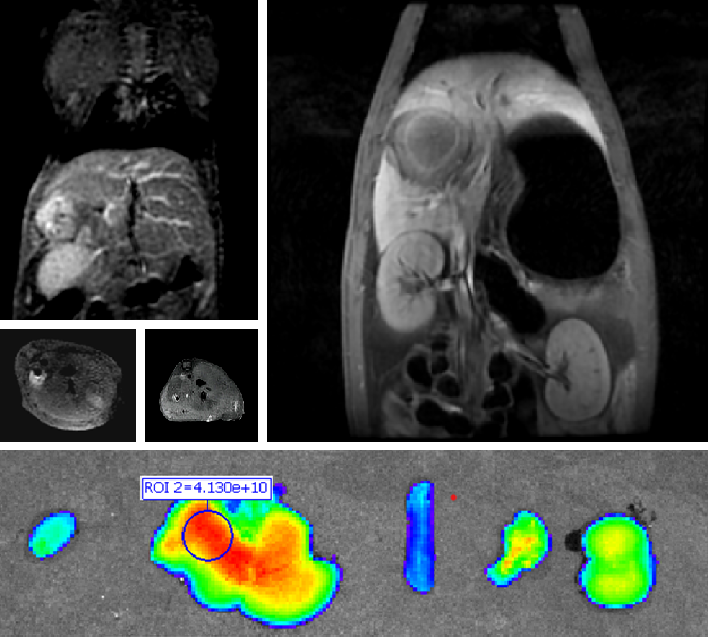

PL002是浙江普利藥業(yè)有限公司研發(fā)的熒光/磁共振雙模態(tài)造影劑,開發(fā)熒光/磁共振雙模態(tài)造影劑成為提高原發(fā)性肝癌手術(shù)效率的有效方案。雙模態(tài)造影劑的熒光成像能力可用于肝癌術(shù)中熒光導航,而磁共振增強能力可用于在術(shù)前判斷肝臟代謝能力,推測腫瘤及肝臟對造影劑的攝取情況,提高腫瘤診斷精度,降低術(shù)前規(guī)劃難度。

PL002相較于吲哚菁綠具有明顯優(yōu)勢。目前吲哚菁綠在臨床使用中存在給藥到手術(shù)時間不確定的問題,可能造成病灶與正常組織對比度不足,影響術(shù)中的病灶的判斷,PL002采用獨特的釓絡(luò)合物與熒光分子共價鍵結(jié)合的分子結(jié)構(gòu)設(shè)計,這種設(shè)計能夠讓醫(yī)生在術(shù)前通過磁共振成像確定造影劑在病灶中的聚集情況,進而針對患者個體情況來對手術(shù)時間進行規(guī)劃。同時,由于PL002體內(nèi)更為穩(wěn)定,在荷瘤小鼠模型中同等條件下熒光成像效果維持時間長于現(xiàn)有熒光造影劑,也保證了其在臨床應(yīng)用中具有更寬的手術(shù)窗口。

使用雙模態(tài)造影劑可以為手術(shù)醫(yī)生提供更加豐富的診斷信息,降低術(shù)中的決策壓力,避免過度切成,增加發(fā)現(xiàn)微小病灶的可能性,最終實現(xiàn)患者的全面獲益。此外,相較于傳統(tǒng)熒光造影劑,PL002的安全性更高、體內(nèi)更為穩(wěn)定,成像效果更佳,為其臨床使用提供了有效的支持。